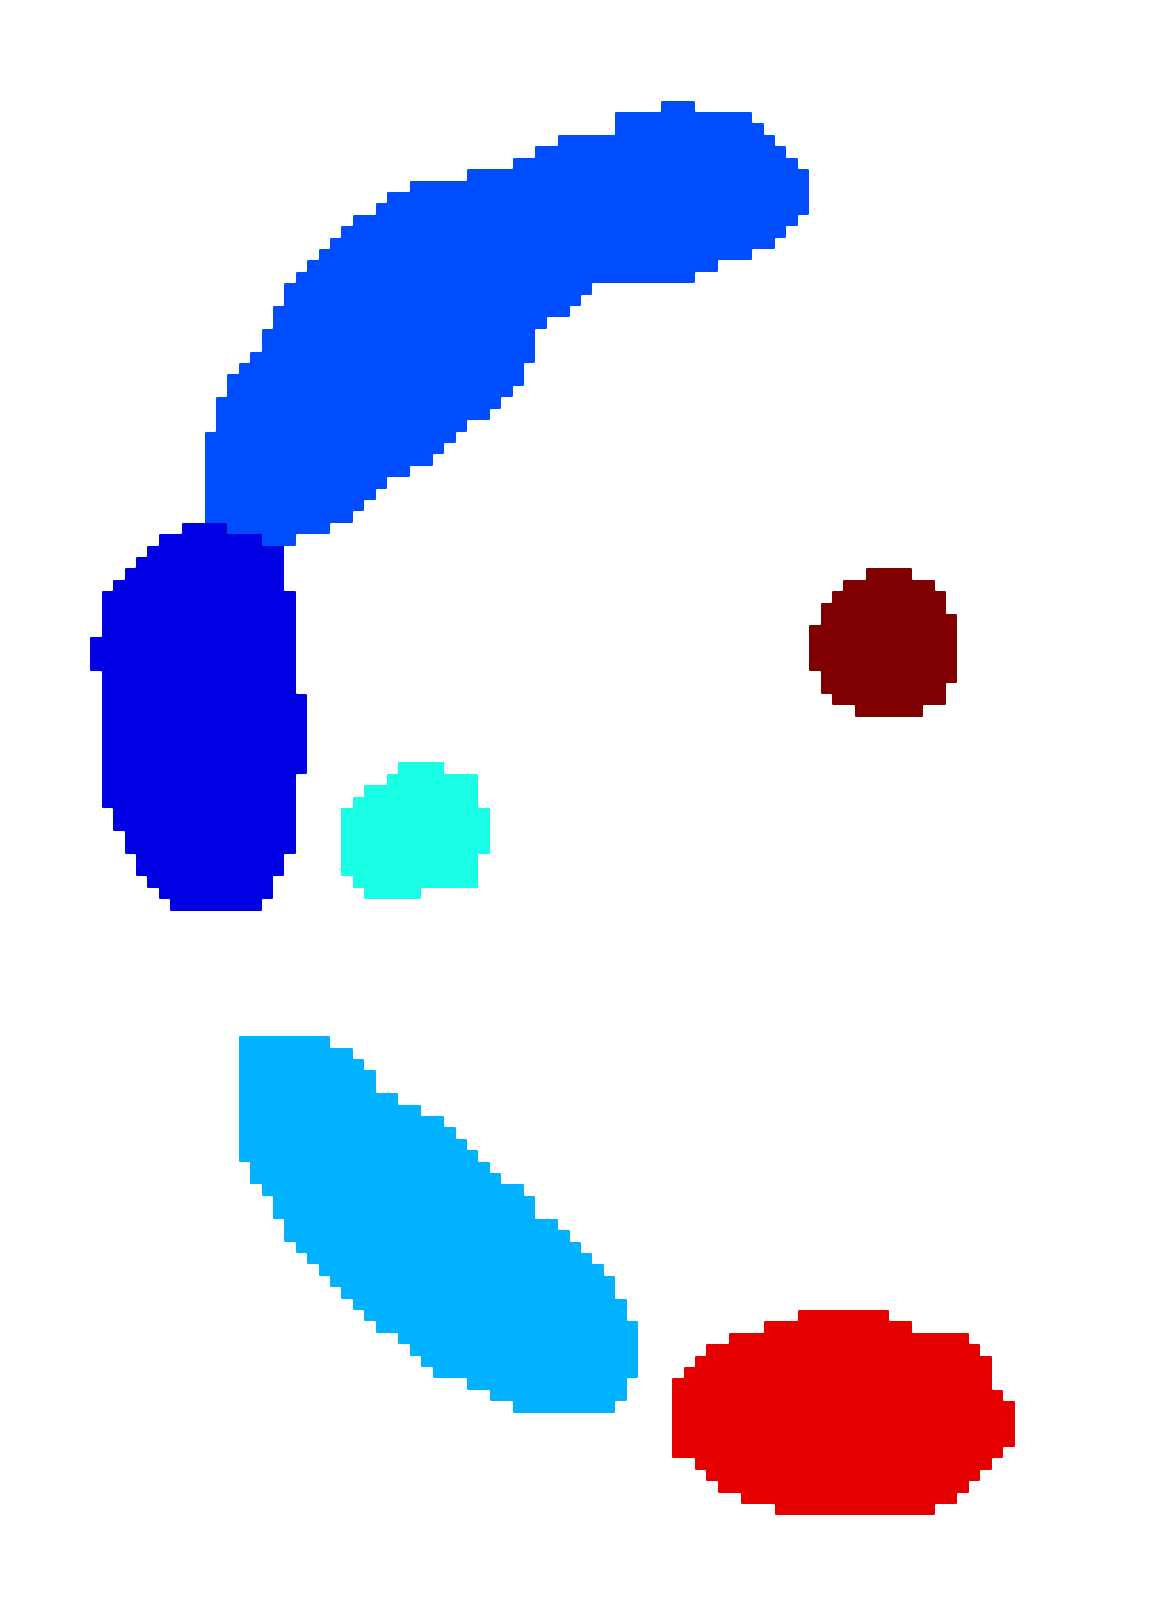

The scalar vesselness responses of both HCP and PC images are determined using the state-of-the-art Frangi filter (FFR) [8], and Optimally Oriented Flux (OOF) [12]. Also, the connected vesselness map (CVM) and the associated tensor field (TF) are synthesized for the same dataset using VTrails. The connectedness of the considered scalar maps is qualitatively assessed and the TF is inspected as proof of concept in section 3.1.

3.1 Connectedness of the Vesselness Map

Fig. 3 shows the connectedness of vessels recovered from state-of-the-art vascular enhancers and curvilinear ridge detectors FFR and OOF together with the proposed CVM for the synthetic HCP and the real PC images.

On the synthetic phantom, FFR shows a fragmented and rough vesselness response in correspondence of irregularly shaped sections of the structure. Also, the response at the bifurcation is not smoothly connected with the branches (triangular loop). Conversely, OOF recovers the phantom connectedness at the branch-point, and the vesselness response is consistent along the tortuous curvilinear section, however ghosting artifacts are observed as the shape of the phantom becomes irregular (C-like) or differs from a cylindrical tube. Also, close convoluted structures, which change scale rapidly in the HCP, produce inconsistent responses of OOF (fig. 3). CVM shows here a strongly connected vesselness response in correspondence of both regular and irregular tubular sections, with local maxima at structures’ mid-line. The connectedness of the structures is emphasized regardless the complexity of the shape, and it resolves spatially the tortuous curvilinear ‘kissing vessels’ without additional ghosting artifacts, despite the smooth profile.

Similar results are observed on the PC dataset: FFR has a poor connected response in the noisy and low-resolution image. Vessels are overall enhanced, however thin and fragmented structures remain disconnected. Overall, the vesselness response is not uniform within the noisy structures, where maximal values are often off-centred. A more consistent response is obtained from OOF, where the connectedness of vessels is improved. Maximal response is observed at the mid-line of vessels, however, noise rejection is poor. CVM strongly enhances here the vessel connectivity. The fragmented vessels of PC have a continuous and smooth response in CVM with higher values and a more defined profile. Large vessels shows solid connected regions with local maxima at mid-line as in OOF. Conversely from OOF, CVM shows improved noise rejection in the background.

The respective tensor fields (TF) synthesized on both HCP and PC show consistent features. The TF’s characteristics are in line with the connectedness of CVM: enhanced and connected vessels are associated with high anisotropy, whereas background areas show a predominant isotropic component.